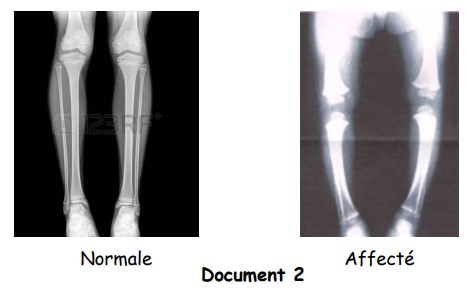

Un enfant atteint d’une fatigue générale et d’un manque de développement avec une jambe en forme d’arc est examiné par un médecin. Le médecin a mesuré la quantité de certaines vitamines. Les résultats sont représentés dans la table du document 1.

Le médecin a effectué une radiographie à la jambe de l’enfant pour le comparer avec un individu normal. Les résultats sont illustrés dans le document 2.

- Quel est le nom de cette maladie ?

- Expliquer l’effet du manque de vitamines indiquées dans le document 1 sur l’état de l’enfant qui est représenté dans le document 2.